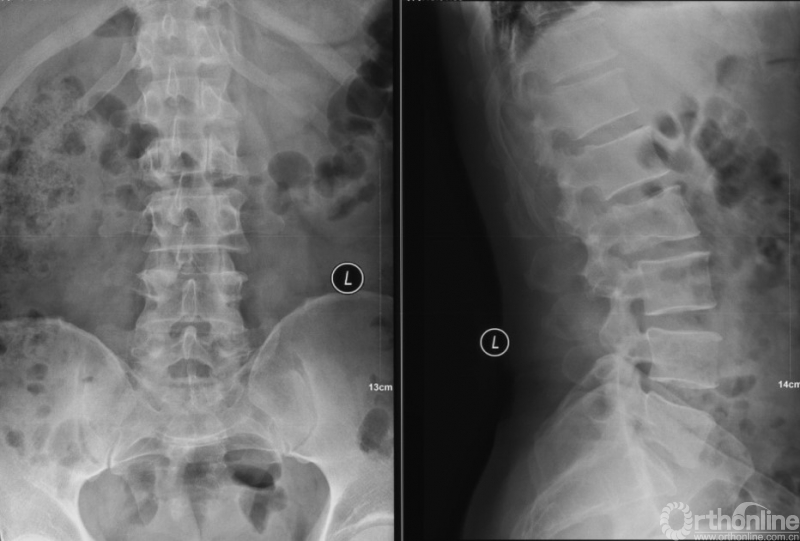

影像学资料

PVP治疗

术后6个月

入院影像学资料